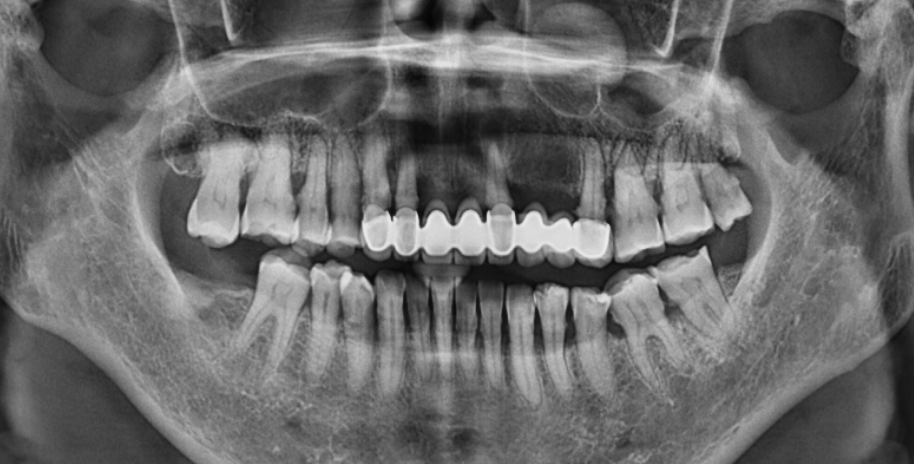

我院口腔医生接诊后口内检查示:口腔卫生状况不良,局部牙龈颜色暗红,后牙区少量菌斑、软垢。龈下牙石较多(++),切牙向唇侧移位,呈扇形散开排列,出现牙间隙。影像学检查:全口牙槽骨出现不同程度吸收,尤其上排牙吸收至根中下段。

影像学检查